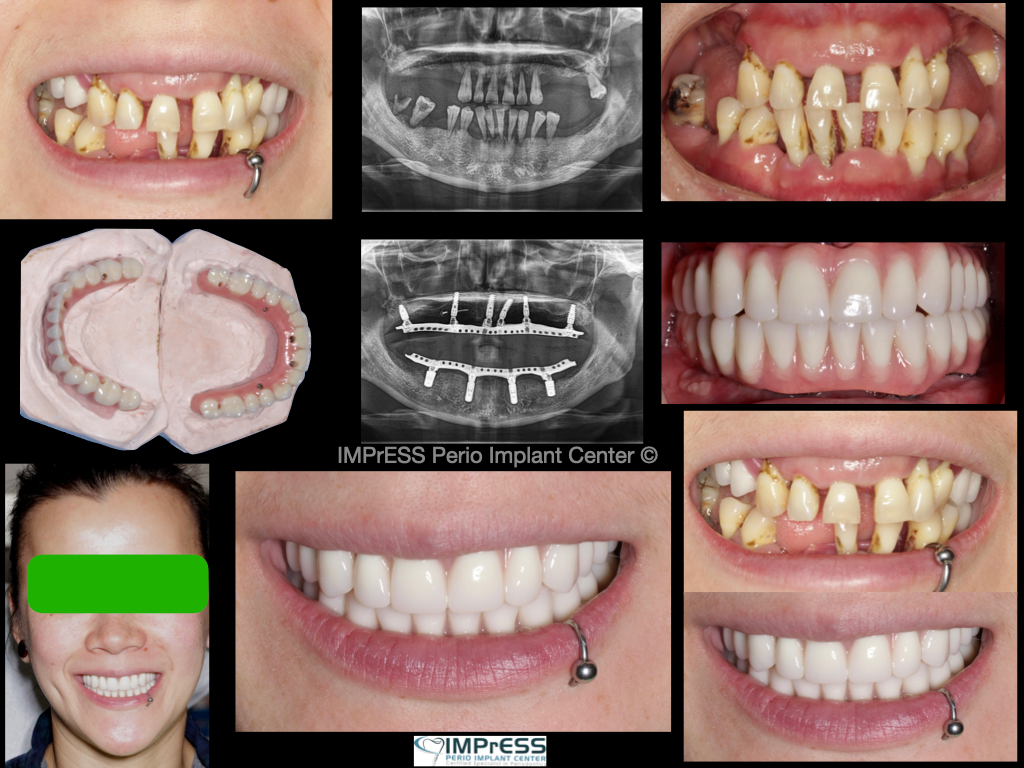

Before & Afters of Dental Implant Patients

Complete Dental Implant Cases Gallery

A minimally invasive solution with a fixed full-arch implant restoration for high patient satisfaction, Fixed (Non-removable) Same-Day-Teeth, providing immediate function and aesthetics

General Disclaimer: The results in the photographs are examples only and do not imply any certainty of the result of a procedure, and all outcomes are subject to the circumstances of the individual patient.